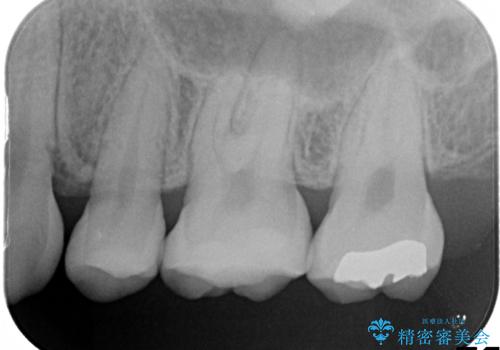

- 他院で虫歯になっていると指摘され来院されました。適合の良いゴールドインレーによる治療がされていましたが、違う部分が虫歯になってしまっていました。審美性の良いセラミックインレーを希望されました。

ゴールドインレーを除去し、その下で広がっていた虫歯をきれいに取り除きました。

一度治療した歯も再び虫歯になる可能性があるので、定期的なチェックが大切になります。